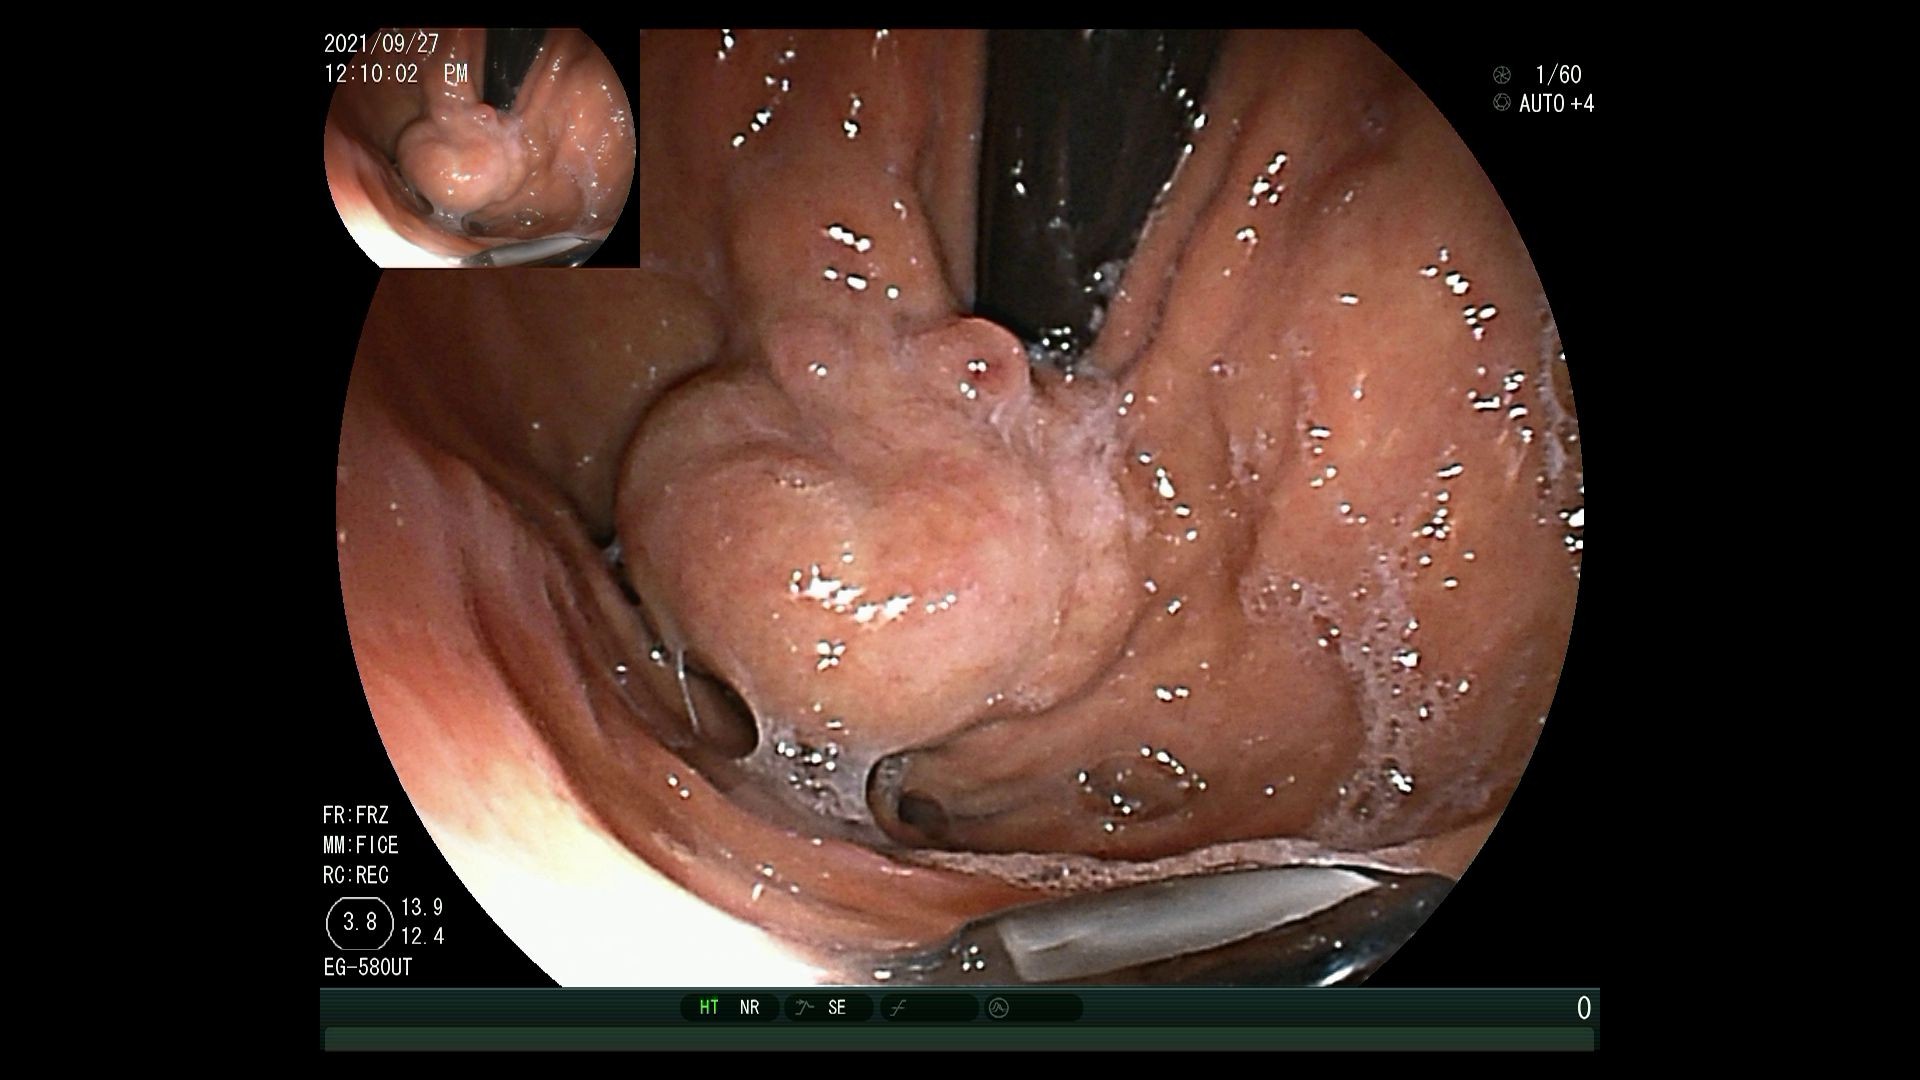

1)胃镜检查发现胃底静脉曲张,直径约4cm,表面见白色血栓头。